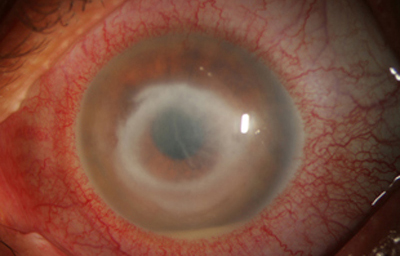

Superficie corneal irregular y grisácea, (Fig. 1, 2) con opácidades granulares en parche y formación de líneas epiteliales elevadas de aspecto granular (Fig. 3), que pueden arborizar dando imágenes de pseudodendritas. Opacidades superficiales satélites. (Figura 4) Inyección ciliar. Ulceración epitelial variante. (Figura 5).

Fig. 2 Síntomas de 25 días evolución